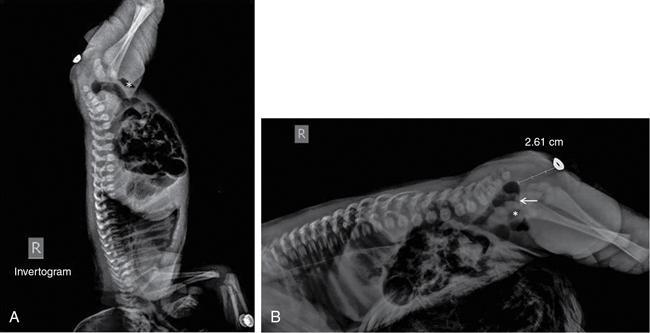

MISCELLANEOUS PAEDIATRIC RADIOGRAPHY – TECHNIQUES AND INTERPRETATION: SKELETAL SURVEY Padma V. Badhe The skeletal survey, generally performed in children, is a set of radiographs done in order to evaluate the entire skeleton. A skeletal survey, commonly used to evaluate skeletal dysplasias, acquired metabolic disorders and suspected child abuse, is still the key radiological investigation for the same. Hence, an explicit understanding of the technique along with the common disorders forms the basis of making a diagnosis in these paediatric pathologies. A skeletal survey is done for various skeletal dysplasias, non-accidental injury (battered baby syndrome) and suspected child abuse. It can also be done in cases of metabolic bone diseases, disseminated infections, multiple myeloma, eosinophilic granuloma. It is also used in evaluation of metastatic bone diseases and polyarticular arthropathy. Orthogonal views of the skull, spine, pelvis and one extremity are taken, preferable in standing position. For preterm babies/newborns, AP and lateral views of babygram may be taken. Projections: For skeletal dysplasias: Additional views: Both extremities may be taken if epiphyseal abnormalities and limb asymmetry is present. Focused views for specific pathologies may be taken. When a diagnosis remains uncertain, 1 year follow up is usually recommended. For preterm babies/newborns: AP and lateral views of babygram may be taken with additional specific views for extremities. For suspected non-accidental injury (NAI): AP and oblique view of chest is taken for better evaluation of the ribs. AP view of abdomen with pelvis. Both upper and lower limbs are evaluated. In lower limbs, two projections in AP and lateral (one with both femur including hip and knee joints; and another for foot and ankle) is taken. AP and lateral views of whole spine, skull. Oblique view of hands. A babygram should be avoided in cases of NAI, as subtle fractures are easily missed. Proper legal documentation while taking the views is very important and ideally two health care professionals must be present. For metabolic disorders: entire skeletal survey is usually not required. Specific views of hands, knees and spine may be taken with additional views depending on the suspected pathology. Centring point: Varies according to the part being examined. Angulation, collimation and orientation: Varies according to the part being examined. Images must be well collimated to obtain lower radiation dose. Detector size: Varies according to the part being examined: 8″ × 10″, 10″ × 12″, 11″ × 14″. Exposure: Ideally high kVp images are taken to reduce radiation dose. But in suspected NAI, low kVp/high mA images are recommended to better demonstrate findings. SID (Source Image Distance):100 cm Grid: Grids are not routinely used to image spine, pelvis, skull and abdomen in children. Radiation dosage: 0.3–3 mSv Essential image characteristics: Adequate spatial resolution, high signal to noise ratio, low kVp (50–70) for high contrast should be done. Excellent bone and soft tissue details are required. The presentation of skeletal dysplasia can range anywhere from minimal stunting of growth and bowing of limbs to severe dwarfism and multiple fractures. Knowledge of the commonly encountered dysplasias with an approach to arrive at a diagnosis is vital in any Radiologist’s practice The following flow chart summarizes the classification of important skeletal dysplasia: The following table summarizes the various dysplasias affecting the axial skeleton: TABLE 7.5.1.1 The following flow chart summarizes the working approach to skeletal dysplasias: Osteopetrosis (Albers-Schonberg disease/Marble bone disease) (Fig 7.5.1.1): Osteopetrosis clinically presents with anaemia/thrombocytopenia or cranial nerve compression. Radiological features include generalized increase in bone density with loss of medullary space. However, cortico-medullary appreciation with cortical thinning is also rarely seen. Bone within bone appearance with Erlenmeyer flask deformity is also noted. Pyknodysostosis (Figs. 7.5.1.2 and 7.5.1.3): patient presents with short stature. Unlike osteopetrosis, there is no anaemia. Radiographs show generalized increase in bone density with preserved medullary canal. There is mandibular hypoplasia with obtuse angle. Acro-osteolysis is also a feature. Dental caries with osteomyelitis of the jaw may be seen. Sclerosing dysplasia presenting as wavy undulating new bone formation. Usually monomelic, lower limb and along one side. The classic appearance is described as Dripping candle Wax sign. It is a Sclerosing dysplasia with radiological features of symmetric juxta-articular involvement in epimetaphyseal region. They are 1–10 mm in diameter and uniform in size. No metabolic activity is seen on bone scans. This skeletal dysplasia shows diffuse decrease in bone density with paper-thin cortex. Fractures heal in normal time but shows callus with poorly cellular matrix. Wormian bones and enlarged sinuses may be seen. Codfish vertebra (Biconcave vertebra) may be seen. Metaphyseal corner fractures are not seen in osteogenesis imperfecta that helps to differentiate it from battered baby syndrome. There are four types of OI out of which type one is most common (Figs. 7.5.1.6 and 7.5.1.7). The radiological features of MPS include Osteopenia and Universal platyspondyly. The intervertebral disc spaces are maintained. Proximal pointed metacarpals is an important radiological finding. Hurler’s syndrome show anteroinferior beaking with short and wide metacarpals. Varus deformity of humerus is characteristically seen in Hurler’s syndrome (Fig. 7.5.1.8). Mental retardation & corneal clouding is seen in Hurler’s syndrome whereas these Hunter’s disease has normal intelligence with no corneal clouding. Morquio’s syndrome shows central beaking (Fig 7.5.1.9). This skeletal dysplasia shows normal bone density with rhizomelic limb shortening and normal trunk. Narrowing of spinal canal is classically seen with decrease in the Interpedicular distance caudally. Other radiological features include trident hand (separation of middle & third fingers), Champagne glass pelvis (short, flat ilia and small sciatic notch), bullet nose vertebra and overexpansion of skull with narrow foramen magnum (Fig. 7.5.1.10). This skeletal dysplasia is characterized by normal bone density with dwarfism and normal craniofacial skeleton. The interpedicular distance is normal. There is severe platyspondyly with anterior tonguing (disappears at older age). Other radiological features include increased disc space, short stubby metacarpals, small irregular epiphysis and widened metaphysis. Anterior tonguing is a feature of Pseudoachondroplasia. This form of skeletal dysplasia involves the spine and epiphyses (Fig. 7.5.1.11). There is normal bone density with rhizomelia. Spine and Pelvis can be involved. Premature osteoarthritis can be seen. The other characteristic features include Platyspondyly and small irregular epiphysis. There are two forms Spondyloepiphyseal dysplasia Congenital and Spondyloepiphyseal dysplasia Tarda. Spondyloepiphyseal dysplasia Congenita is Autosomal dominant and shows pear-shaped vertebrae. Spondyloepiphyseal dysplasia Tarda is X Linked recessive with heaped up vertebrae. It has two forms. The first form is Conradi Hunermann syndrome which is autosomal dominant characterized by asymmetric limb shortening with metaphyseal flaring (Fig. 7.5.1.12). The Autosomal recessive form is Fatal in first few years. Rickets: Rickets refers to deficient mineralization of the growth plate in the paediatric population due to deficiency of vitamin D. In an immature skeleton, there is abnormal mineralization at the zone of provisional calcification in the metaphysis due to osteoid deposition resulting in widening of the growth plate. The features of rickets include fraying, splaying and cupping (Fig. 7.5.1.13). Fraying denotes indistinct margins of the metaphysis whereas splaying denotes widening of metaphyseal ends. Term ‘Cupping’ is used for increased concavity of the metaphysis. These findings are typically seen involving areas of active growth (e.g. distal femur and proximal tibia in the knee) Bowing is a result of associated osteomalacia leading to weakening of weight-bearing lower limb bones. Other bone deformities such as genu valga, genu varum, protrusio acetabuli can also be seen. The lower ribs may also be drawn inwards inferiorly by the attachment of the diaphragm this is called Harrison’s sulcus. Scurvy: Scurvy is a result of dietary deficiency of Vitamin C (ascorbic acid). The classic presentation is that of a patient with an increased bleeding tendency and osteopenia with poor wound healing. Features of scurvy include generalized osteopenia with cortical thinning termed as ‘pencil-point’ cortex. Other radiological findings include the periosteal reaction due to subperiosteal haemorrhage. Expansion of the costochondral junctions occurs forming scorbutic rosary. Bleeding into the joint spaces may result in hemarthrosis. Circular, opaque radiologic shadow surrounding epiphyseal centres of ossification may result from bleeding (Wimberger ring sign) (Fig. 7.5.1.14). Frankel line may be seen. It represents dense zone of provisional calcification. Lucent metaphyseal band is seen underlying Frankel line called as Trümmerfeld zone. Metaphyseal spurs may be seen that result in cupping of the metaphysis (Pelkin spur). Pelkin fracture (metaphyseal corner fracture) can also be seen. Images obtained must be of good resolution with adequate bone and soft tissue details. Additional views: They have already been described in positioning. CT Brain in can be done in cases of NAI to look for subdural hematomas. A skeletal survey is the first-line imaging modality for evaluation of skeletal dysplasia, nonaccidental injury and metabolic bone diseases. The skeletal survey must be tailored according to the respective indication. It helps to characterize syndromic patterns in skeletal dysplasias, with evaluation of complications. In cases of diagnostic dilemmas, additional focused view and occasionally yearly follow-up is recommended. A high index of suspicion is needed in utilizing skeletal survey as a diagnostic modality in NAI. At the same time, one must also remember the legal and social implications of making this diagnosis. BABYGRAM Babygram is a colloquial term used for a radiograph of the whole body of a newborn or just the chest and abdomen (thoracoabdominal babygram) on a single image. As the name suggests it is a rather non-targeted study. It is most commonly requested after line placement. Evaluation of skeletal abnormalities in a deceased foetus is typically performed using anteroposterior and lateral views of a babygram. It helps in pointing out skeletal causes of death in stillborn or dead foetuses. This will help the treating physician and parents understand the reason for baby’s death. This will also help in future genetic counselling of the couple. Sometimes chest or abdominal radiographs of the baby are requested but due to radiographers error or inexperience with small babies, there is inclusion of the region not to be assessed leading to a false babygram. Babygram is most frequently done after line placement in neonates, to view the position of the umbilical vein or artery catheter and to confirm appropriate placement. It is a useful modality in skeletal dysplasias (Fig. 7.5.1.15) like osteogenesis imperfecta, thanatophoric dysplasia and chondrodysplasia punctata. It can also be used for skeletal deformations probably caused by foetus akinesia and in cases of Caudal regression syndrome. In stillborn foetuses, it is used for evaluation of skeletal dysplasias prior to an autopsy (Fig. 7.5.1.16). It is also used in screening for surfactant deficiency and in cases of Necrotizing Enterocolitis in preterm babies where it can help to see the bowel dilatation, intramural and portal venous gas. It can be done in aneuploidies like trisomy 18 and in cases of sudden infantile death syndrome. All the essential equipment and room need to be prepared including the exposure factor. This should be done prior to placing the baby on the table to prevent any neonatal heat loss. Ensure that the baby is correctly identified. Give brief explanation to the patient’s parents regarding the procedure, its risks and benefits. Ensure that the accompanying relative is not pregnant (if female). Parents/guardians/nurses should be instructed to hold the baby with arms above the head and legs straight down. Sandbags/tapes can be used to immobilize the baby. Avoid taking the radiograph when baby is crying. Normal appearance: The endotracheal tube should lie in the lower third of trachea, distance can vary with position of baby’s head. Umbilical artery catheter has an inferior dip along the internal iliac artery, which then turns superiorly along the aorta. The tip should lie in the mid-thoracic aorta (T6–T10) or lower (L3–L4) away from aortic branches to prevent any thrombosis. Umbilical venous catheter does not have the inferior curvature, but rather a posterolateral angulation to the right near the liver through the ductus venosus. The tip should lie in the superior IVC or right atrium at T8/T9 vertebral level (Fig. 7.5.1.17). Portal venous gas may be seen initially after insertion. In a stillborn foetus, the approximate gestation age of the foetus and corresponding ossification centres must be known. In early gestation, the lack of appearance of an ossification centre may be mistaken for skeletal dysplasia. Both chest and abdomen should be included. In a rotated patient, the distance between the spinous process to medial end of clavicles will be asymmetric. The medial end of clavicle should overlap the lung apex, if above, suggests lordotic image. Motion artefacts to be reduced as much as possible. A crying neonate may result in an expiratory film, and hence must be evaluated accordingly. In evaluation of skeletal dysplasias in the newborn, additional views of skull and hand have to be obtained. Baby gram is a useful diagnostic investigation for position of the paediatric umbilical catheters. It helps in general survey in skeletal dysplasia (Fig. 7.5.1.18). It is a simple, effective study in deceased foetus for diagnosis and further counselling, sometimes obviating the need for an autopsy. As baby gram is a non-targeted study, it increases the dose of radiation for the baby. As the exposure settings remain same for the entire body of the baby, the quality of the image decreases. This increases the chances of missing subtle findings. The babygram in a neonate is currently used to localize umbilical catheters. In stillborn fetuses, it is still an important study for documenting and confirming skeletal dysplasias. Understanding the normal appearance as per gestation age and patterns of various common skeletal dysplasias is essential for evaluation. Being a non-targeted study, it should not be used as an alternative study to evaluate the chest or abdomen considering radiation exposure and poorer image quality. INVERTOGRAM Invertogram was first described by Wangensteen and Rice in 1930. It was used as a first investigation to be ordered in evaluation of infants with clinically diagnosed or suspected Anorectal Malformation (ARM). ARM is a serious but surgically treatable congenital malformation with approximate incidence of 1 in 5000 live births. Though the diagnosis of this condition is based on clinical history and physical examination, imaging plays an important role in deciding the type of ARM, and associated complications to aid in management. International classification of anorectal malformations is as follows. Syndromic association is seen as a part of VACTERL defects, trisomy 21 13 and 18, Klippel Feil syndrome, cat eye syndrome etc. The main indication of Invertogram is to evaluate anorectal malformation in a neonate. A radio-opaque marker is placed over the external anal opening. Infant is held inverted by holding both thighs, maintaining this posture for at least 5 minutes before taking an X-ray in true lateral position (Fig. 7.5.1.19). Exposure is made during inspiration. The Invertogram should ideally be done 24 hours after birth as, the rectal gas may not reach the terminal segment if study is done too early. Pubo-coccygeal line (PCL) is drawn from upper border of pubic symphysis (which corresponds to centre of pubic bone on lateral X-ray) to sacrococcygeal junction. I point is the inferior most point of ischial ossification centre. A line which is drawn parallel to PC line passing through the I point is called I line. ‘A’ point is represented by marker placed at anal pit. The position of rectal pouch gas shadow is observed with respect to these lines and appropriate diagnosis is made (Fig. 7.5.1.21). A diagnosis of high ARM is made when gas shadow of rectal pouch is cranial to PCL. If rectal pouch gas shadow is in between PCL and I line, it is called as intermediate ARM and if it is caudal to I line, it is diagnosed as low ARM. Gas in urinary bladder or vagina or beaking of gas shadow of rectal pouch indicates fistula into one of these sites. Associated congenital abnormalities like spinal defects are also looked for in the invertogram (Fig. 7.5.1.22). Invertogram done too early (less than 24 hours) may not demonstrate rectal gas. Meconium plugging the terminal segment gives false position of the rectal gas. Positioning can cause discomfort to child and an irritated crying child actively contracts the sphincter muscles, pushing the gas shadow higher. Rectum may be pulled cephalad due to gravity in inverted position. The rectal gas may escape through an associated fistula. Erroneous interpretation can also occur due to sacral anomalies and when gas in vaginal cavity is misinterpreted as distal rectal gas. Both ischial bones should superimpose and terminal blind loop should be well distended. It is an easily available modality and can be done quickly, does not require additional equipment. It has lesser radiation dose as compared to CT invertogram. It provides a rough guide as to the type of ARM and decides management. Higher localization of obstruction due to various causes like meconium plugging, imaging done too early etc. as described above in pitfalls. It is more uncomfortable to the baby as compared to the prone cross-table lateral view, and a crying baby contracts the puborectalis leading to erroneous results. K. L. Narasimharao et al. modified the technique and proposed cross-table lateral view for evaluation of infants with ARM’s which has shown equal or better information and has now replaced invertogram (Fig. 7.5.1.23). Prone cross-table lateral view is considered equivalent or even better in determining the level of anomaly. Positioning is in this view is prone in genupectoral position (at least for 3 minutes). It is taken in true lateral and during inspiration. The lines used to delineate types of ARM is essentially the same as in an invertogram. It is preferred over invertogram as relatively easy positioning of the infant and less discomfort allows for better cooperation of neonate during the study. It also eliminates the effect of gravity. ARM with fistula is better delineated as, in an invertogram, fistula/gas is at the highest level and gas may escape through it. CT invertogram is another modality that delineates anatomy better but is rarely used. In the era of cross-section imaging, MRI and USG have opened new modalities for accurate diagnosis of ARM, but invertogram being readily available, inexpensive, quick and cost-effective is used as first investigation for evaluating a patient with suspected or confirmed case of ARM. Cross-table lateral view has replaced invertograms as it is more patient-friendly and equally effective. UPPER GASTROINTESTINAL SERIES Rushit S. Shah An upper gastrointestinal (GI) study is a radiographic examination of the GI tract from the pharynx to the ligament of Treitz after oral administration of contrast agent. The use of upper GI studies is gradually declining with the increasing availability of paediatric endoscopy and the challenge for the modern radiologist to work in conjunction with the surgeon and gastroenterologist to select the right patients for an upper GI series. However, the upper GI series remains the key for demonstrating many anatomical abnormalities. The upper GI series is also useful in evaluating gastro-oesophageal reflux in conjunction with 24 pH monitoring. The upper GI examination is useful in evaluating many conditions including but not limited to:

Indication

Patient positioning

Technical factors

Normal appearances and variants

Essential image characteristics (Fig. 7.5.1.20)

Pathological appearances

Pitfalls